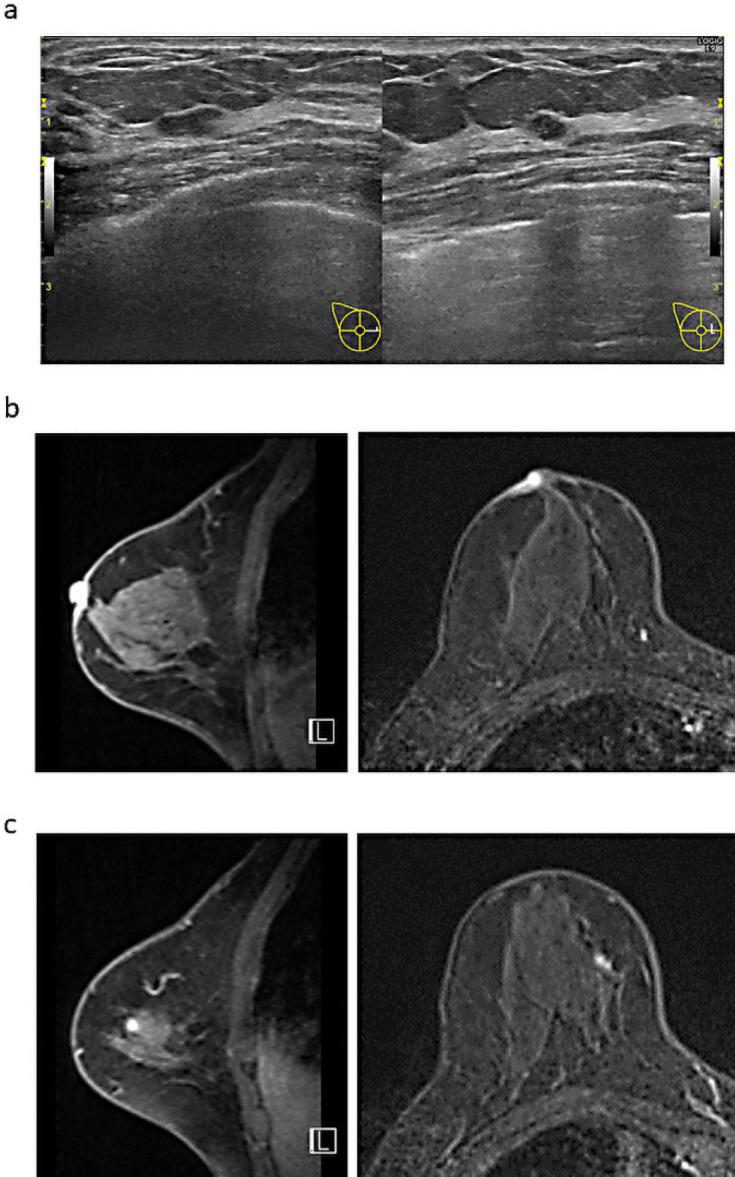

Bowen's disease is a squamous cell carcinoma in situ that commonly develops on the trunk, arms, or legs and has not spread beyond the top layer of skin. It seldom develops on the nipple. We report a patient who presented with Bowen's disease of the nipple and had a concurrent breast cancer identified in the ipsilateral breast after careful examination. Histopathological examination of the surgical specimen after mastectomy confirmed the diagnoses.

鲍恩病是一种原位鳞状细胞癌,通常发生于躯干、手臂或腿部,尚未扩散至皮肤表层以外。它很少发生于乳头部位。我们报告一例乳头鲍恩病患者,经仔细检查后在同侧乳房发现同时存在乳腺癌。乳房切除术后手术标本的组织病理学检查证实了诊断。